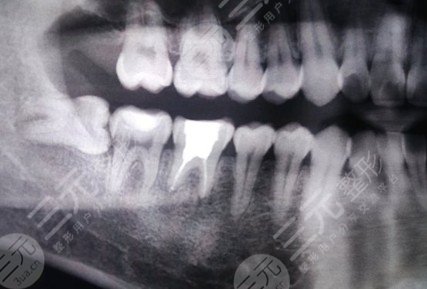

The cost of root canal treatment at the Affiliated Stomatological Hospital of Nanchang University should usually vary depending on the anterior and posterior teeth. In addition, root canal treatment requires the use of special materials and instruments and requires an out-of-pocket project. Depending on the number of root canals in the root canal, the cost of root canal treatment for each tooth is different. There are generally 3-4 root canals in the back teeth, and the cost of treatment is about 1500 yuan. The items that may be included in the treatment process and medical insurance items, such as abnormal and changing teeth found during root canal treatment, require the application of special materials and instruments, and the corresponding number of treatments will also increase, so the cost of root canal treatment will be an option for the treatment of pulpitis and apical periodontitis, that is, root canal treatment is required after pulp inflammation.

Root canal treatment includes ordinary root canal treatment, in the Affiliated Stomatological Hospital of Nanchang University, there will also be a complex root canal treatment specialty, ordinary root canal treatment may be carried out by some young doctors, people, because it is not difficult to consult the affected tooth, the cost will be cheaper. If it is an ordinary doctor, it is a doctor who is a few years younger than him, and cannot be treated. For example, teeth can be more complex. Complex root canal specialties may require special instruments, equipment, and medications, which can be costly. The exact cost depends on the condition of the teeth.

For example, the Affiliated Stomatology Hospital of Nanchang University has only one tooth for a single root canal, and the cost of root canal treatment is relatively cheap. There may be three or four teeth in the back, and even some people may have five or six variations, so the cost of root canal treatment will be relatively high.